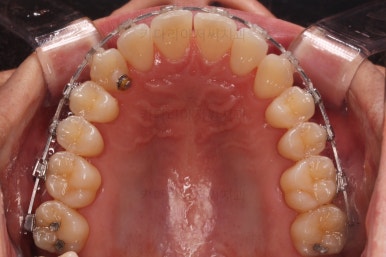

부산비수술교정 키다리아저씨치과에서 시행한 이번 치료의 결과입니다.

옆모습이 주걱턱 느낌이 많이 없어졌고 볼록하던 아랫입술도 뒤로 들어갔어요. 앞니가 거꾸로 물리지 않게 되어 웃거나 말하는 모습도 자연스러워졌어요.

아랫니 갯수가 모자라고 중앙이 맞지 않았고 짝이 안맞는 상황이었으나 비교적 잘 마무리를 했어요.

거꾸로 물리는 상황이 개선되었기 때문에 앞니나 어금니의 교합은 이전과 비교할 수 없을만큼 좋아졌지요.